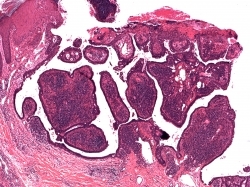

Syringocystadenoma Papilliferum: 33% arise in association with a nevus sebaceous, 10% may coexist with a BCC or trichoblastoma. A subset of cases has a deletion of 9q22 PTCH gene and 9q21 (p16). Histologically they present as surface invagination of glandular cords composed of one to two layers of cuboidal cells associated with a fibrovascular stroma with numerous plasma cells. Cystic spaces may form within which are free floating islands which are peripherally lined by cuboidal cells with an inner core composed of loose connective tissue, blood vessels and numerous plasma cells.

Fig 1 Syringocystadenoma papilliferum. Characteristic low-power morphology of a squamous epithelial border enclosing tall papillary projections with a dense infiltrate within their cores.

Fig 2 Syringocystadenoma papilliferum. The epithelium is double layered and the underlying stroma is rich in plasma cells.

Fig 3 Syringocystadenoma papilliferum. Superficially, the double-layered apocrine epithelium is replaced by squamous epithelium